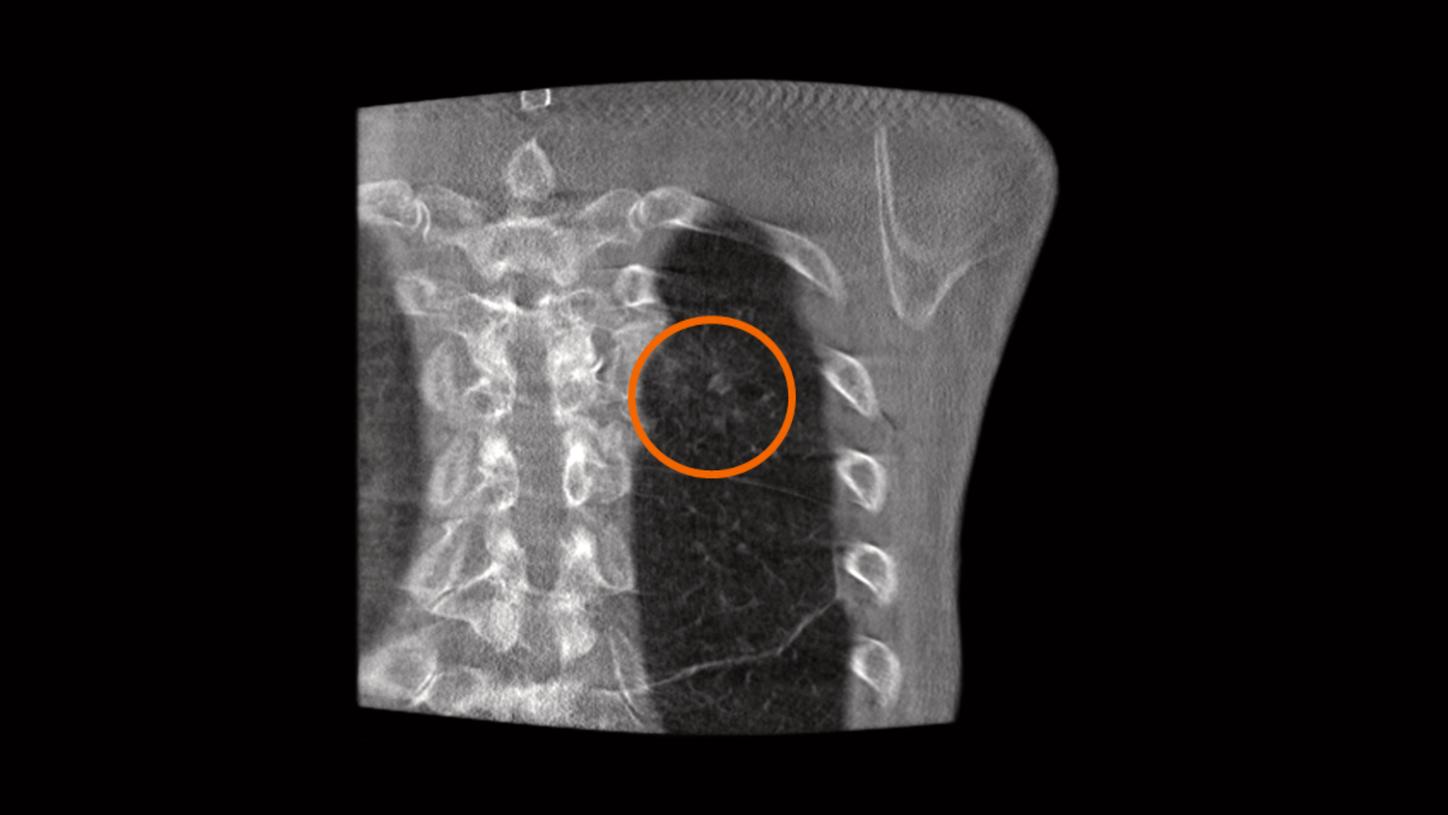

Visualisation syngo DynaCT

de petites artères hépatiques distales. Avec l’autorisation de l’école de

médecine d’Hanovre, Allemagne

Une imagerie 3D simple et précise, dans de nombreuses conditions

Générez des acquisitions 3D avec une haute résolution spatiale et en contraste des tissus mous, quel que soit votre intervention. Avec une vitesse de rotation atteignant 95°/s, les systèmes ARTIS icono sont capables d’acquérir des images syngo DynaCT (= ConeBeam CT) en seulement 2,5 secondes, pour une réduction des artéfacts de mouvement1.

L'imagerie 3D simple et précise facilite la planification des procédures avec un fort niveau de confiance. L’utilisation de syngo DynaCT per-procédure peut également réduire les risques d’effets secondaires indésirables, comme l’embolisation non ciblée1.